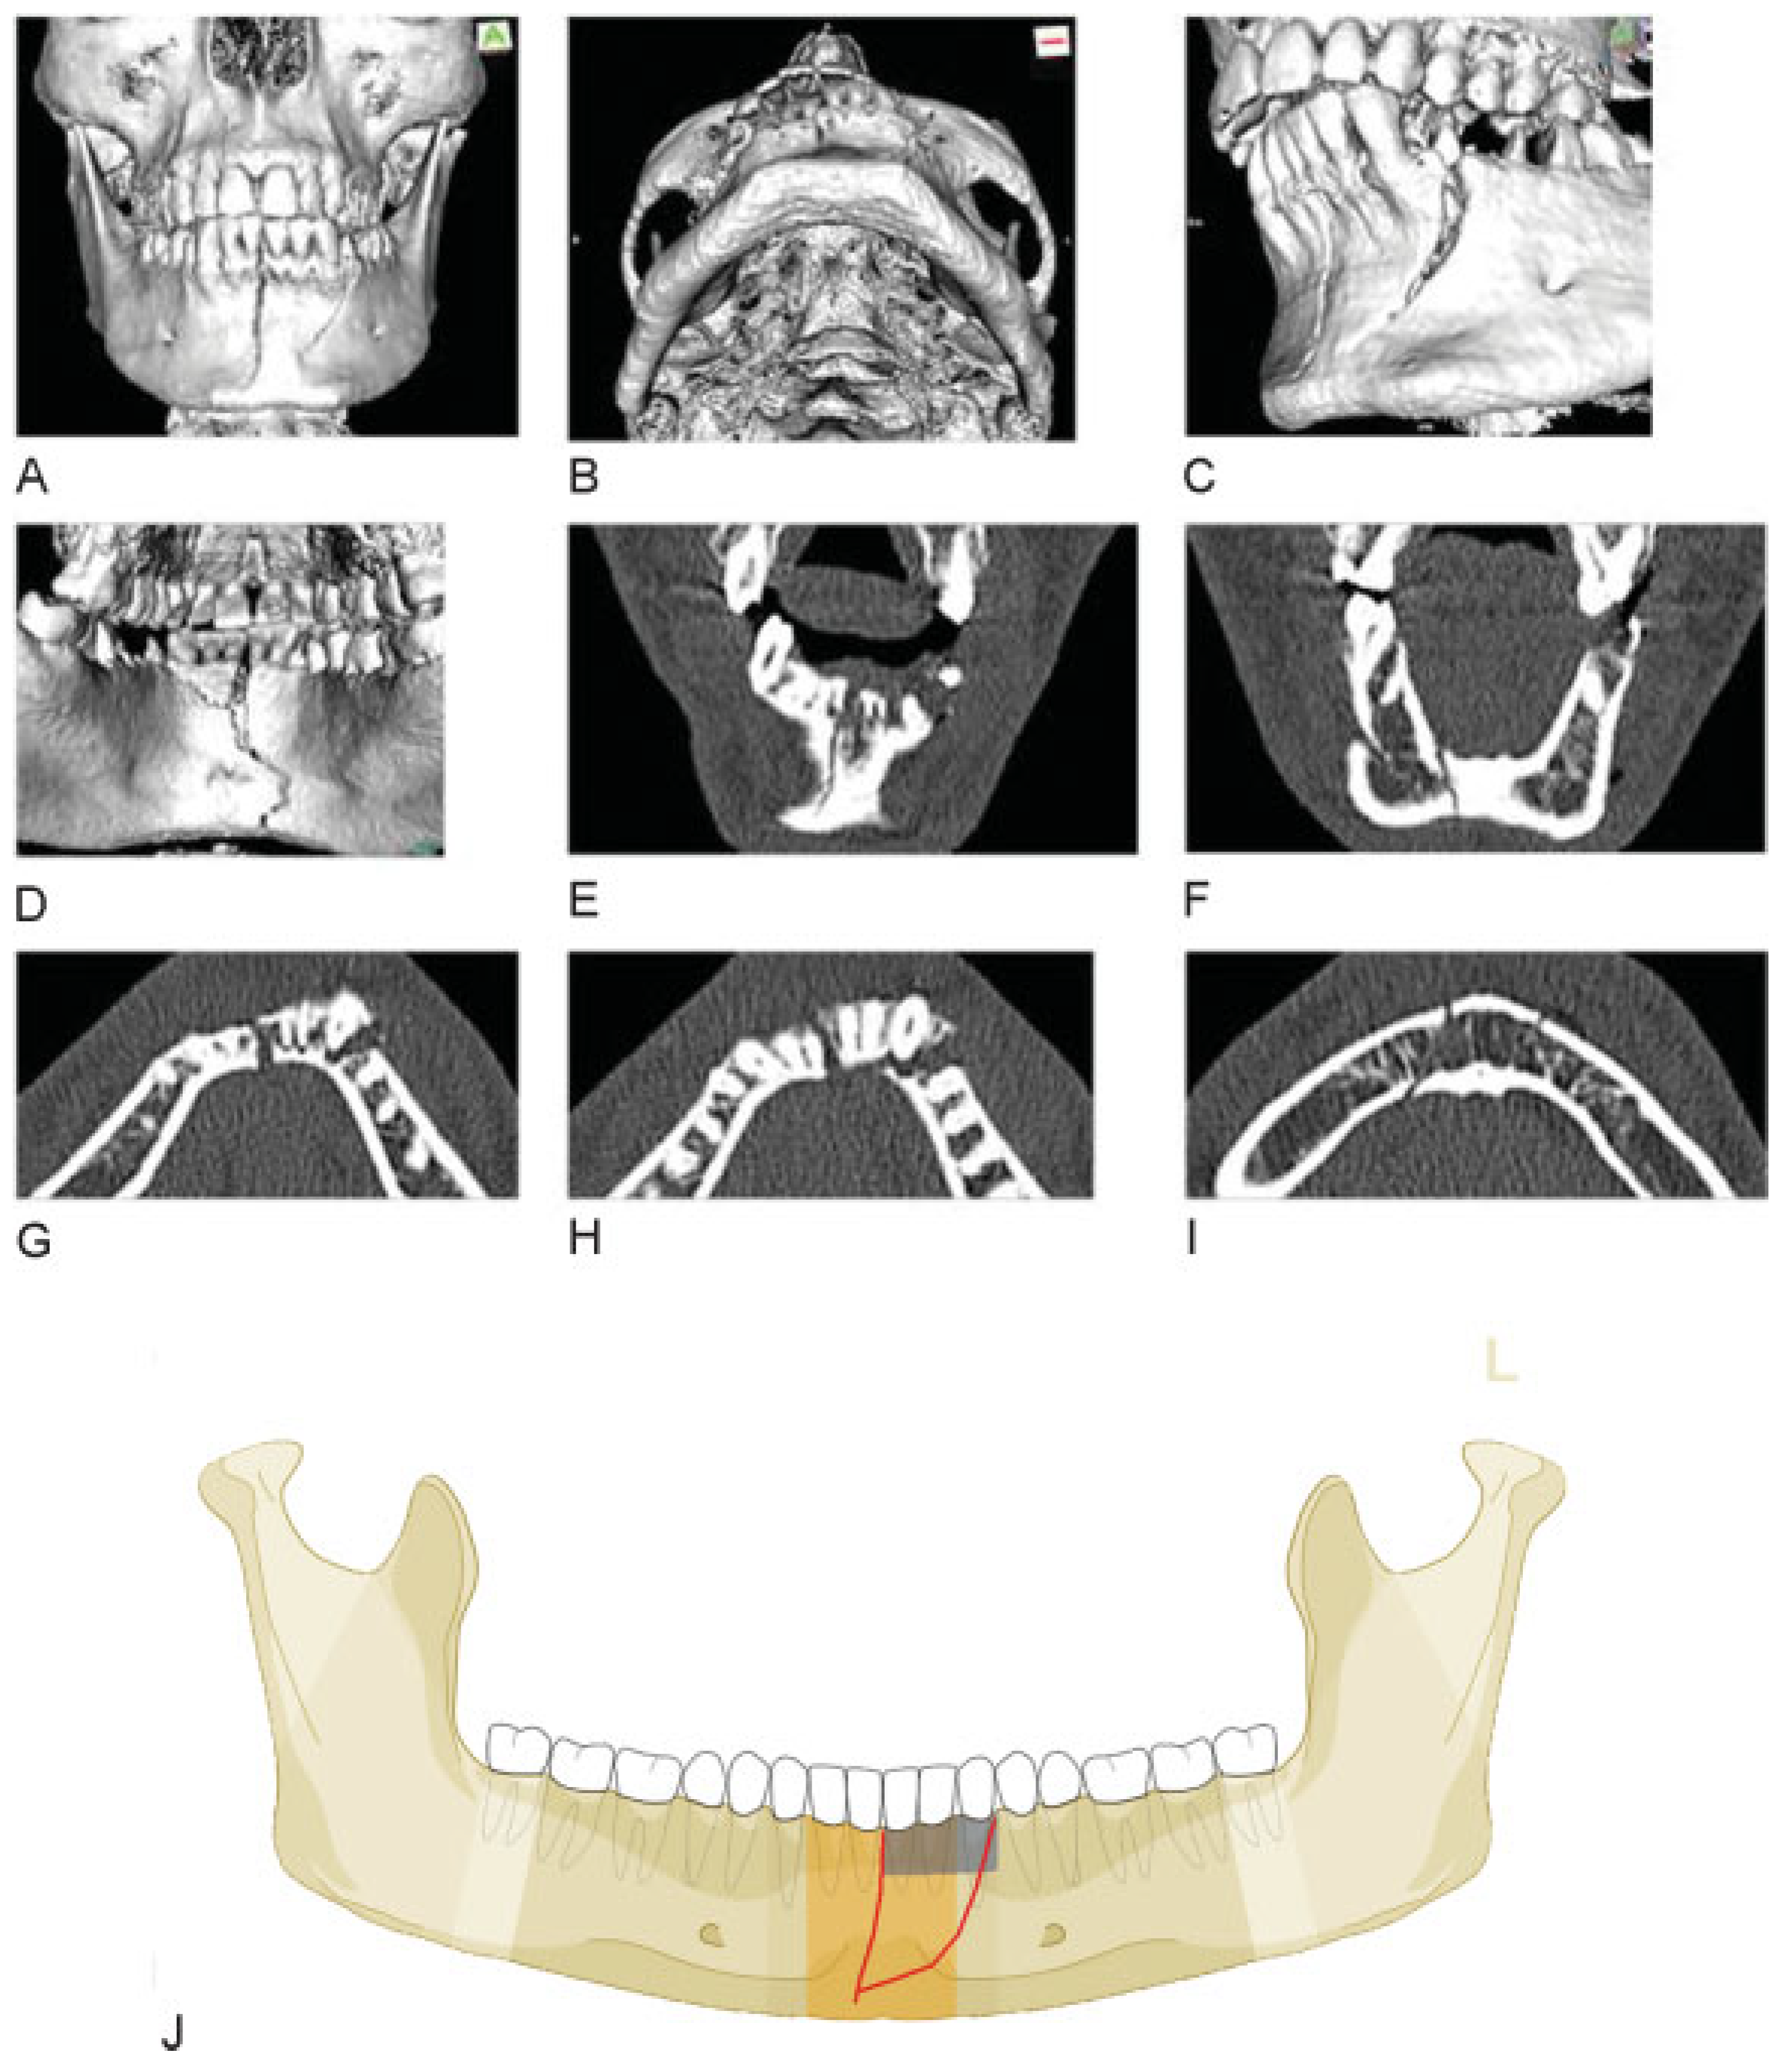

Figure 8.

Two fracture lines or one line in conjunction with alveolar process fracture. (A–I) Imaging: CTscans 3D reformatted overviews frontal, basal and in details (oblique left, lingual view); frontal and axial slices. Narrative description: On the outer surface two fracture lines can be identified: a vertical midline fracture and an oblique fracture line between the premolar region on the left and the mental protuberance or the supramental groove, respectively. From the lingual aspect only one fracture line is visible, which extends in a curvilinear course over the full vertical height of the symphyseal region. There is a second through-shaped fracture line embracing the alveolar process 31, 32, 33. The frontal CT scan slices confirm the presence of a single continuous fracture line over the full height of the mandible only. The axial CTscan slices reveal a large wedge-shaped intermediate fragment which involves both cortices at the level of the alveolar process and tapers into a monocortical layer along the outer surface towards its inferior tip. The outlines of the fracture do not coincide with an alveolar process fracture. The configuration corresponds to a fragmentation grade 1. (J) Code level 3: 91 S1a. This case example CMTR-91-026 is made available electronically for viewing using the AOCOIAC software at www.aocmf.org/classification.